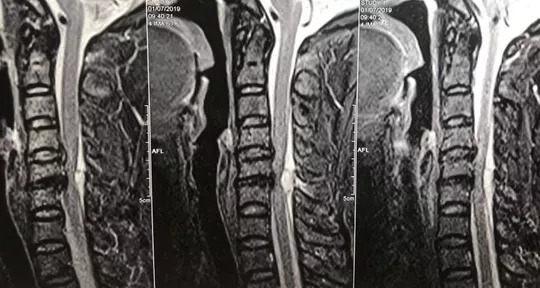

Hình ảnh khối máu tụ lớn chèn ép ống tuỷ là nguyên nhân gây liệt cho bệnh nhân

Sau khi thăm khám, bệnh nhân được chỉ định chụp cộng hưởng từ để tìm nguyên nhân. Kết quả cho thấy bệnh nhân có một khối máu tụ lớn đang chèn ép nặng cột sống cổ và là nguyên nhân gây liệt hai chân của bệnh nhân. Ngay trong đêm, bệnh nhân được mổ cấp cứu. Sau 2 giờ phẫu thuật, bệnh nhân đã được giải phóng khối máu tụ lớn trong cột sống cổ gây chèn ép tuỷ thần kinh. Sau hơn 1 tuần điều trị, bệnh nhân vừa được xuất viện.